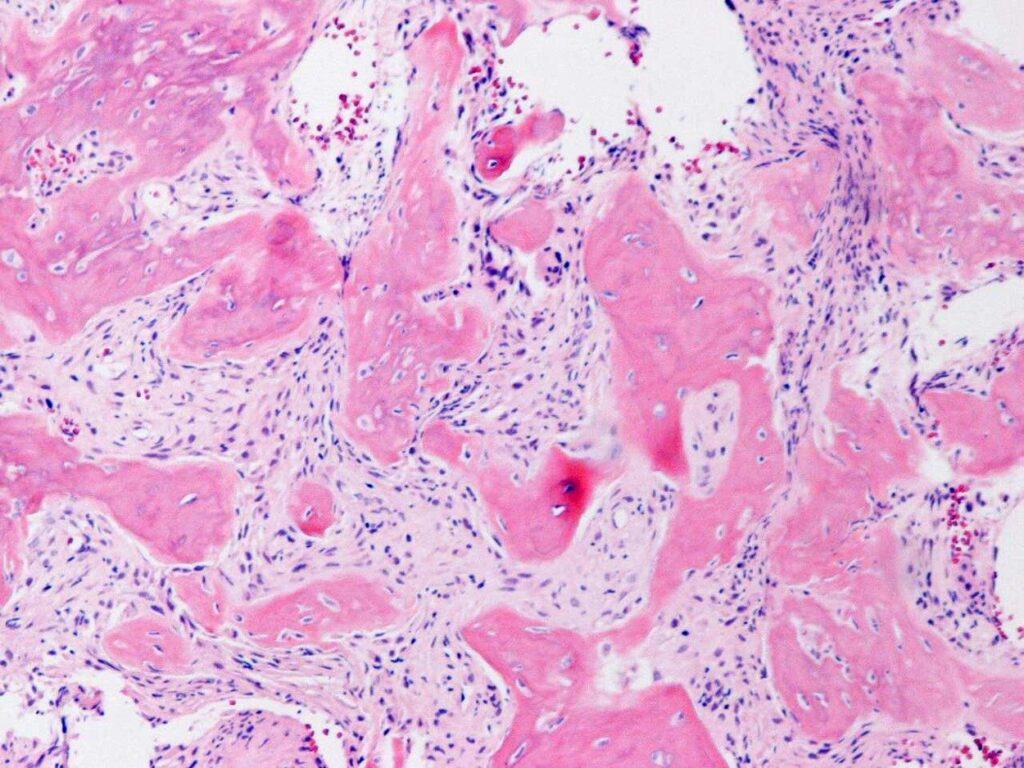

Microscopic

• Display bundles of spindle cell proliferations with variable osteoid production, low cellularity, low mitotic rate, and minimal pleomorphism (Fig. 9 & 10).

• The presence of infiltrative margins and the absence of marked cellular atypia helps to differentiate low grade intraosseous osteosarcoma from benign entities.

Fig. 9 & 10: Microscopic Pathology. Low and high power views with irregular woven bone trabeculae in a moderately cellular fibrous tissue. Atypical cells displaying hyperchromatic nuclei are closely associated with the irregular woven bone trabeculae.